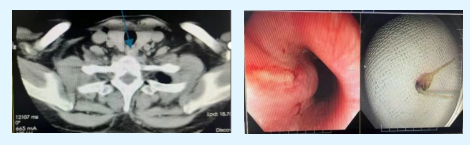

肠道憩室藏粪石

便秘人群需当心

孙大姨因长期便秘反复腹痛,结肠镜检查发现结肠憩室粪石嵌顿,脾胃科医师通过结肠镜巧妙取石,避免憩室炎进一步恶化。肠道憩室是肠壁薄弱处凸起形成的“小口袋”,因肠道压力,肠壁薄弱的地方凸起形成小鼓包,好发于老年人和便秘人群,当食物残渣或粪便进入憩室,水分被吸收会变得很坚硬,憩室内分泌物引流不畅,滋生大量细菌出现憩室炎导致腹痛,若治疗不及时会有憩室穿孔、出血风险。

医生:中老年人如果反复左下腹或者右下腹疼痛,且伴有排便习惯改变,可进行结肠镜检查。